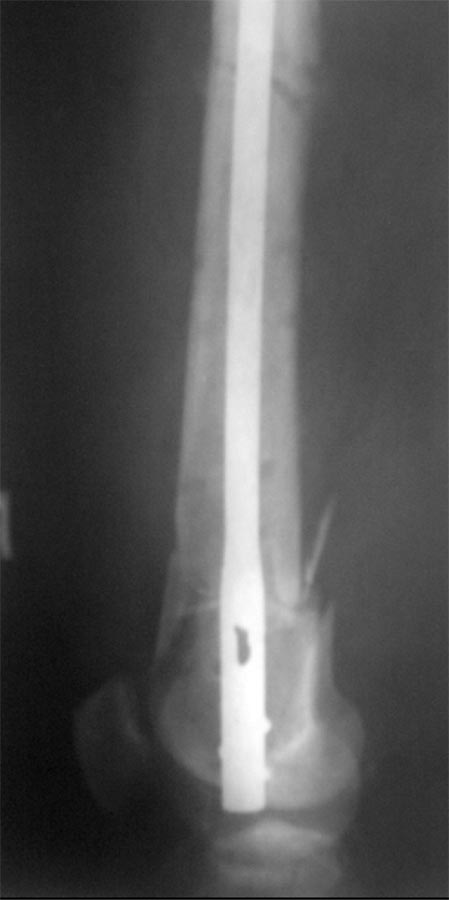

Михаил, кажется конец стержня выстоит в полость сустава, и может вызывать боль. Также следует исключить флеботромбоз и, как следствие, отек нижней конечности.

Думаю, следует разблокировать и добить стержень, и не ставить после этого винты в зону перелома, сейчас они там явно лишние. Перед этим, конечно оценить маркеры воспаления.

Насчет оси - гвоздь в дистальном отломке идет несоосно ему, на уровне перелома гвоздь ближе к латеральной стенке, то есть эпиметафиз смещен медиально. По профилю - и кзади. Похоже, и укорочение есть.

И перелом низкий, и раны немаленькие в области сустава, и стержень выстоит. То есть причины для проблем с движениями есть. Насколько пациент эти проблемы настойчиво и правильно решал, как разрабатывал движения - нет сведений.